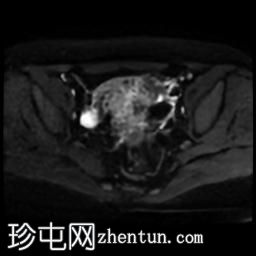

轴位T1加权像

脂肪抑制像

盆腔MRI显示双侧子宫旁多条迂曲静脉,自子宫肌层延伸至盆腔。

此外,左侧附件可见两个充满液体的单纯性囊肿,大小分别约为31 mm和32 mm;右侧附件可见一个卵泡囊肿,大小约为19 mm。

影像学特征符合盆腔充血综合征的诊断,患者为35岁女性,有慢性盆腔疼痛和痛经病史。